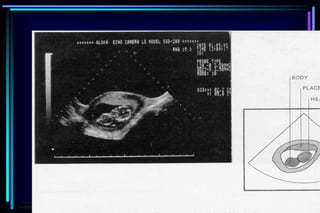

 Fetal number